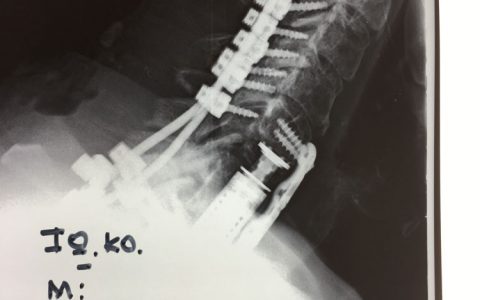

Περίπτωση : Κ.Ι. Κακοήθης Νεοπλασία Αυχενικής Μοίρας Σπονδυλικής Στήλης

Ιστορικό: Ο κύριος Κ.Ι. 69 ετών άρχισε να παραπονείται περί τις αρχές Νοεμβρίου 2017 για πόνο εντοπιζόμενο στην αυχενική περιοχή της σπονδυλικής στήλης χωρίς κάποια προφανή αιτία. Για την αντιμετώπιση του πόνου υποβλήθηκε στην συνήθη συντηρητική αγωγή η οποία περιελάμβανε φυσικοθεραπεία και μυοχαλαρωτικά αναλγητικά φάρμακα. Μια εβδομάδα μετά την έναρξη της φυσικοθεραπείας ο ασθενής αισθάνθηκε